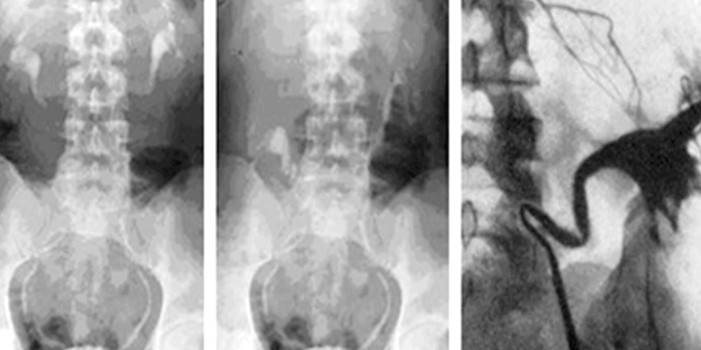

Экскреторная урография при нефроптозе: диагностические изображения